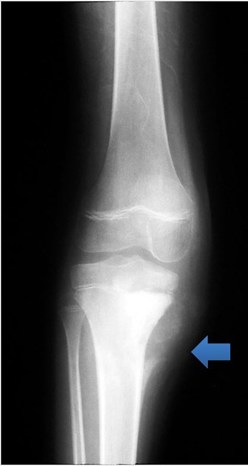

The radiograph below shows the cortex changes and soft tissue swelling (arrow) of osteosarcoma in the proximal tibia